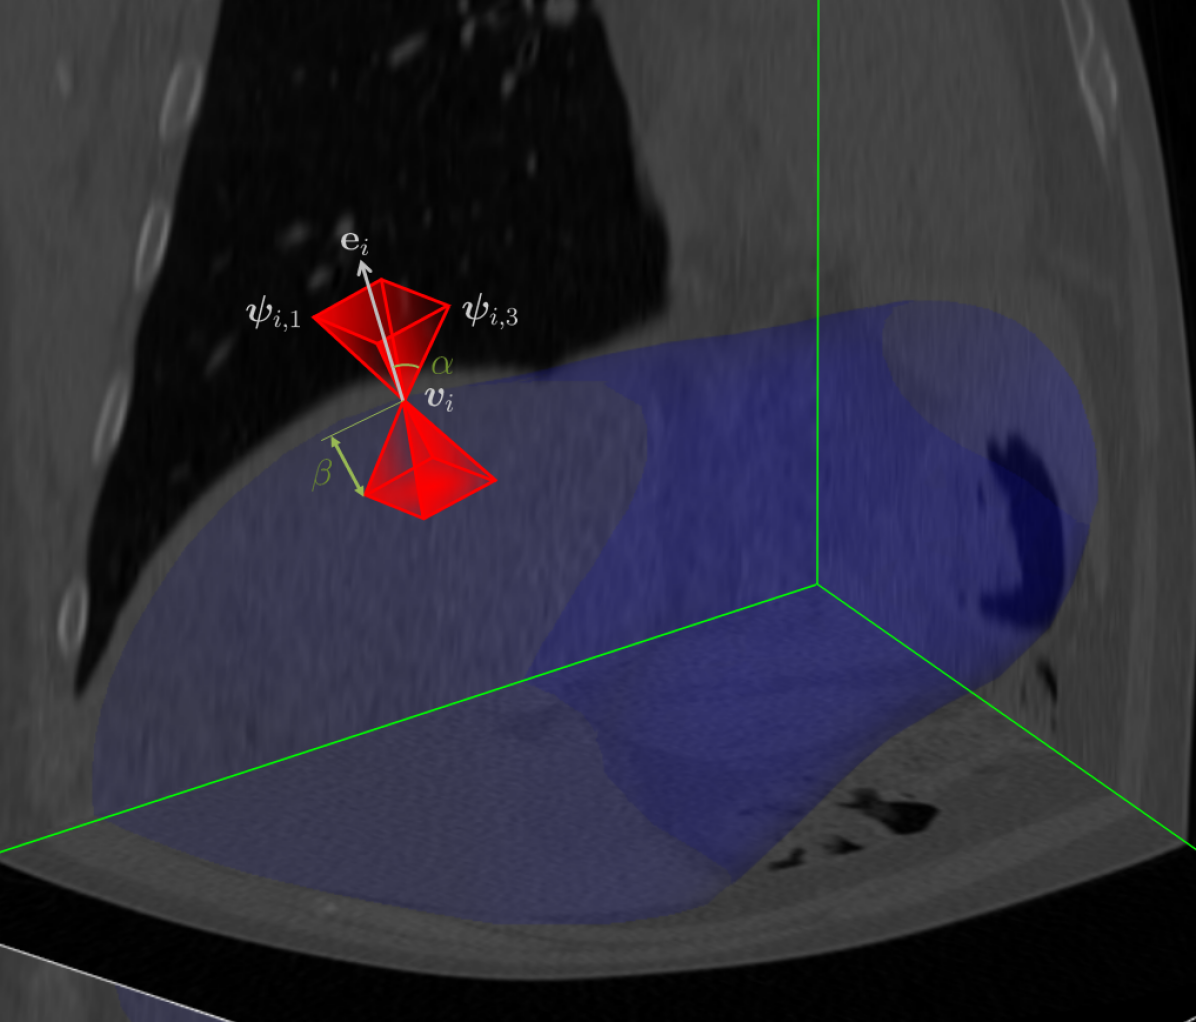

We encode each state, as a concatenation of aperture appearance and associated vertices. We extract the surface mesh 𝐆^^𝐆\hat{\mathbf{G}} of an organ and its associated appearance in the 3D volume 𝐈𝐈\mathbf{I} by sampling the gray valued reconstructed volumetric X-ray image in a cone of vision. We name the cone’s extracted features aperture appearance 𝛀𝛀\mathbf{\Omega}. For each vertex, a symmetric cone of vision is constructed, which tip is at the vertex location and its rotational axis is defined by the vertex’ normal vector. The aperture size α𝛼\alpha is the cone angle for feature sampling. The aperture depth β𝛽\beta defines the cone’s height and maximal capture range of aperture features. The aperture density γ𝛾\vec{\gamma} determines the discrete sampling density in depth and size of the aperture features. For each vertex v^isubscript^𝑣𝑖\hat{\vec{v}}_{i}, its local coordinate frame 𝐞i=[e1,e2,e3]subscript𝐞𝑖subscript𝑒1subscript𝑒2subscript𝑒3\mathbf{e}_{i}=[\vec{e}_{1},\vec{e}_{2},\vec{e}_{3}] is calculated, where e1subscript𝑒1\vec{e}_{1} is the vertex’ normal vector. The boundary of the cone of vision is constructed with angle α𝛼\alpha as well as maximal length β𝛽\beta. Therefore, we can define the boundary of the aperture for each vertex as 𝚿(α,β,γ,𝐆^)=[𝚿i,,𝚿N]𝚿𝛼𝛽𝛾^𝐆subscript𝚿𝑖subscript𝚿N\mathbf{\Psi}(\alpha,\beta,\gamma,\hat{\mathbf{G}})=[\mathbf{\Psi}_{i},\cdots,\mathbf{\Psi}_{\text{N}}], where 𝚿i=[ψ1,,ψ4]subscript𝚿𝑖subscript𝜓1subscript𝜓4\mathbf{\Psi}_{i}=[\vec{\psi}_{1},\cdots,\vec{\psi}_{4}] denotes the vector of the boundary of the aperture cone. We extract the gray values of associated sampling points in the aperture 𝚯𝚯\mathbf{\Theta} and concatenate these features with the coordinates of all vertices 𝐯^^𝐯\hat{\mathbf{v}}, their normal vectors, and the aperture boundary 𝚿𝚿\mathbf{\Psi}. The concatenated features are the aperture appearance 𝛀(𝐯^,𝚯,𝚿|𝐈,𝐆^)𝛀^𝐯𝚯conditional𝚿𝐈^𝐆\mathbf{\Omega}(\hat{\mathbf{v}},\mathbf{\Theta},\mathbf{\Psi}\,|\,\mathbf{I},\hat{\mathbf{G}}). An illustration of aperture appearance extraction is demonstrated in Fig. 1.

Figure 1: The pipeline of our method (left) and illustration of aperture features (right). The training phase steps are blue, testing phase steps are red and joint steps are green. The aperture boundary is illustrated as a red cone, where the blue surface mesh is the current estimate.